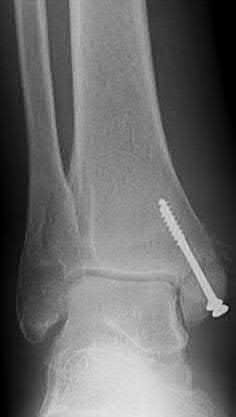

Question 2:

A 28-year-old male sustains a severe hyper-dorsiflexion injury to his ankle in a motor vehicle accident, resulting in a Hawkins Type III talar neck fracture. Which of the following arteries provides the predominant blood supply to the body of the talus, placing it at significant risk for avascular necrosis in this injury?

Correct Answer: Artery of the tarsal canal

Explanation:

The artery of the tarsal canal, which is a branch of the posterior tibial artery, provides the dominant blood supply to the talar body. In a Hawkins Type III fracture (talar neck fracture with subtalar and tibiotalar dislocation), the blood supply from the artery of the tarsal canal, the artery of the sinus tarsi, and capsular vessels are disrupted, leading to an avascular necrosis (AVN) rate approaching 100%.